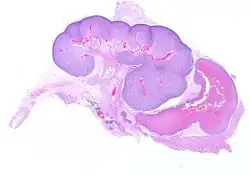

A picture of a fetal kidney taken via virtual microscopy of fetal tissue at 23 wee—I mean, THE KIDNEY OF A CHILD MURDERED BY RADICAL LEFTIST SCIENTISTS!!!